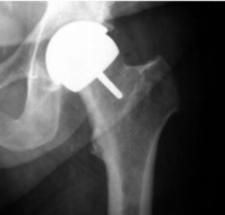

Bei den totalen Hüftendoprothesen (Hüft-TEP) werden in der Regel eine künstliche Hüftpfanne und eine Schaftprothese mit Aufsteckkopf implantiert. Hierfür stehen unterschiedliche Prothesenmodelle und Verankerungsmöglichkeiten (zementiert, zementfrei) zur Verfügung. Eine neuere operative Versorgungsmöglichkeit stellt der Hüftoberflächenersatz dar. Es handelt sich hierbei um ein besonders knochensparendes Prothesensystem, dessen klinischer Einsatz jedoch noch jung ist, sodaß potentielle Vorteile noch nicht abschließend beurteilt werden können.

Bei der zementierten Hüftprothese wird eine anatomisch angepasste Schaftprothese aus einer hochwertigen Edelstahllegierung (CoNi) über Knochenzement in der Markhöhle des Oberschenkelknochens verankert. Der Gelenkpartner zur künstlichen Hüftpfanne besteht in der Regel aus einem Keramikaufsteckkopf.

Als Pfannenersatz wird bei diesem Verfahren eine aus Polyethylen

bestehende Pfannenschale durch den Knochenzement im zuvor aufbereiteten

Pfannenlager befestigt. Vorteil der zementierten Hüftprothesen ist die

jahrelang zurückreichende Erfahrung mit diesen Systhemen, die sich zum

Teil über Jahrzehnte bewährt haben.

Bei der zementfreien Hüftprothese besteht die Schaftprothese aus einer speziellen Titanschmiedelegieung, welche das Anwachsen von Knochen fördert. Den Gelenkpartner zur künstlichen Hüftpfanne bildet ein Aufsteckkopf aus Keramik.

Als

Pfannenersatz wird in das zuvor aufbereitete Pfannenlager eine

subhemisphärische Titanschale eingepresst oder geschraubt, in welche

dann spezielle Polyethylen- oder Keramik-Inlays eingebracht werden.

Bei der Implantation eines Hüftoberflächenersatzes werden die arthrotisch veränderten Gelenkflächen des Oberschenkelkopfes und der Hüftpfanne durch dünne Metallprothesen ersetzt. Der gesunde Knochen des Schenkelhalses bleibt dabei größtenteils erhalten. Die spezielle dafür notwendige Operationstechnik erlaubt im Gegensatz zu den "klassischen" Hüftprothesen keine Minimal invasiven Zugänge. Die Volllastaufnahme ist jedoch sofort möglich und eine schnelle Rehabilitation die Regel.